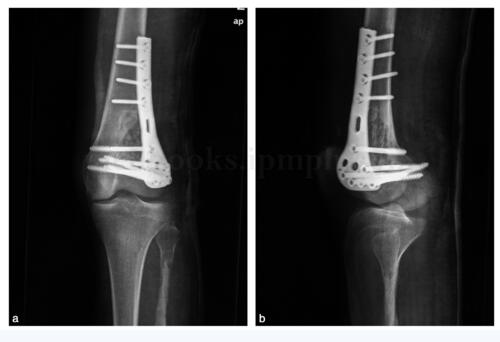

图16‐5 二次术后X 线片a﹒正位,可见填充物及内固定物影;b﹒侧位